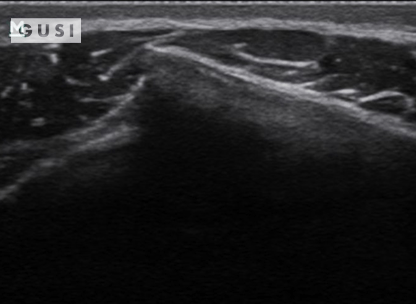

During the 2018 World Taekwondo Junior Championships in Hammamet, Tunisia, a 17-year-old male junior Taekwondo athlete took a fall, landing on his right shoulder. He exhibited a markedly limited range of motion in the affected shoulder and experienced intense pain, leading to suspicions of a dislocation.

A pre-reduction ultrasound (A) of the right shoulder showed a pronounced gap between the humeral head (indicated by a solid arrow) and the glenoid (marked by an open arrow), suggesting an anterior dislocation. Following a shoulder reduction procedure, a post-reduction ultrasound (B) verified the successful realignment of the glenohumeral joint (solid arrow pointing to the humeral head and open arrow to the glenoid).

After the procedure, the athlete displayed a considerably improved range of motion in his right shoulder and his pain levels diminished significantly.